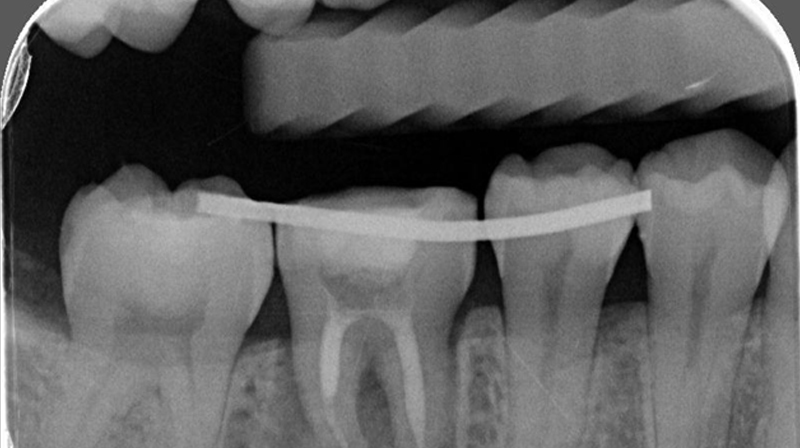

術前評估口腔狀況

術前